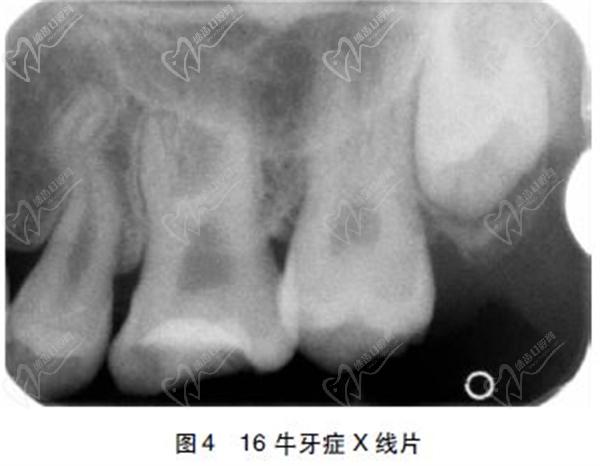

2、牙髓腔扩大:通过X线检查可以发现,牛牙症患者的牙髓腔明显扩大。这是由于在牙齿发育过程中,牙髓腔的发育与牙齿形态发育不匹配所导致的。

2)牙髓腔扩大:通过X线检查可以发现患者的牙髓腔明显扩大,尤其是在根尖部。

3)牙髓底部顶 端位移:X线检查显示牙髓底部向上位移,导致牙髓腔底部与牙齿顶部之间的距离增加。